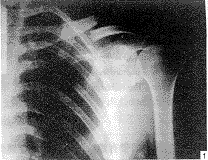

【摘要】 目的 改进锁骨骨折内固定治疗的方法。方法 应用带螺纹的克氏针治疗锁骨骨折34例。结果 随防6~18个月,无一例发生骨折不愈合和克氏针滑脱,所有病例上肢功能恢复良好。结论 该手术操作简单,固定可靠,无畸行愈合,疗效满意。

【Abstract】 Objective To improve method of treating internal fixation forclavicular fractures. Methods Screw-threaded Kirschners wire was used to treat 34 cases of clavicular fractures.Results The patients were followed up for 6 to 18 months, none of whom wasfound to have the delayed union of fracture and the taking off for Kirschners wire and the upper limbs functions recovered well. Conclusion The technique is simple, the effect of reduction good and the fixation reliable, and there is no deformity union.